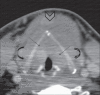

A unique imaging dilemma is presented where vocal fold thickening due to Reinke's edema mimicked tumor invasion of the vocal cords in a known case of thyroid malignancy.